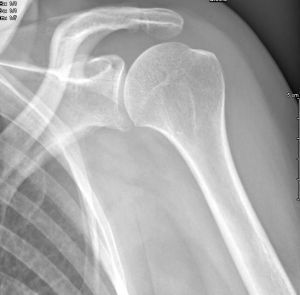

Les radiographies sont fréquemment requises entre autres, pour la recherche d'une fracture dans le cadre d'un traumatisme, les bilans d'arthrose, les bilans statiques, l'étude des poumons au cours d'une radiographie thoracique ...

Réaliser dans différentes positions selon les "incidences" utiles au diagnostic.